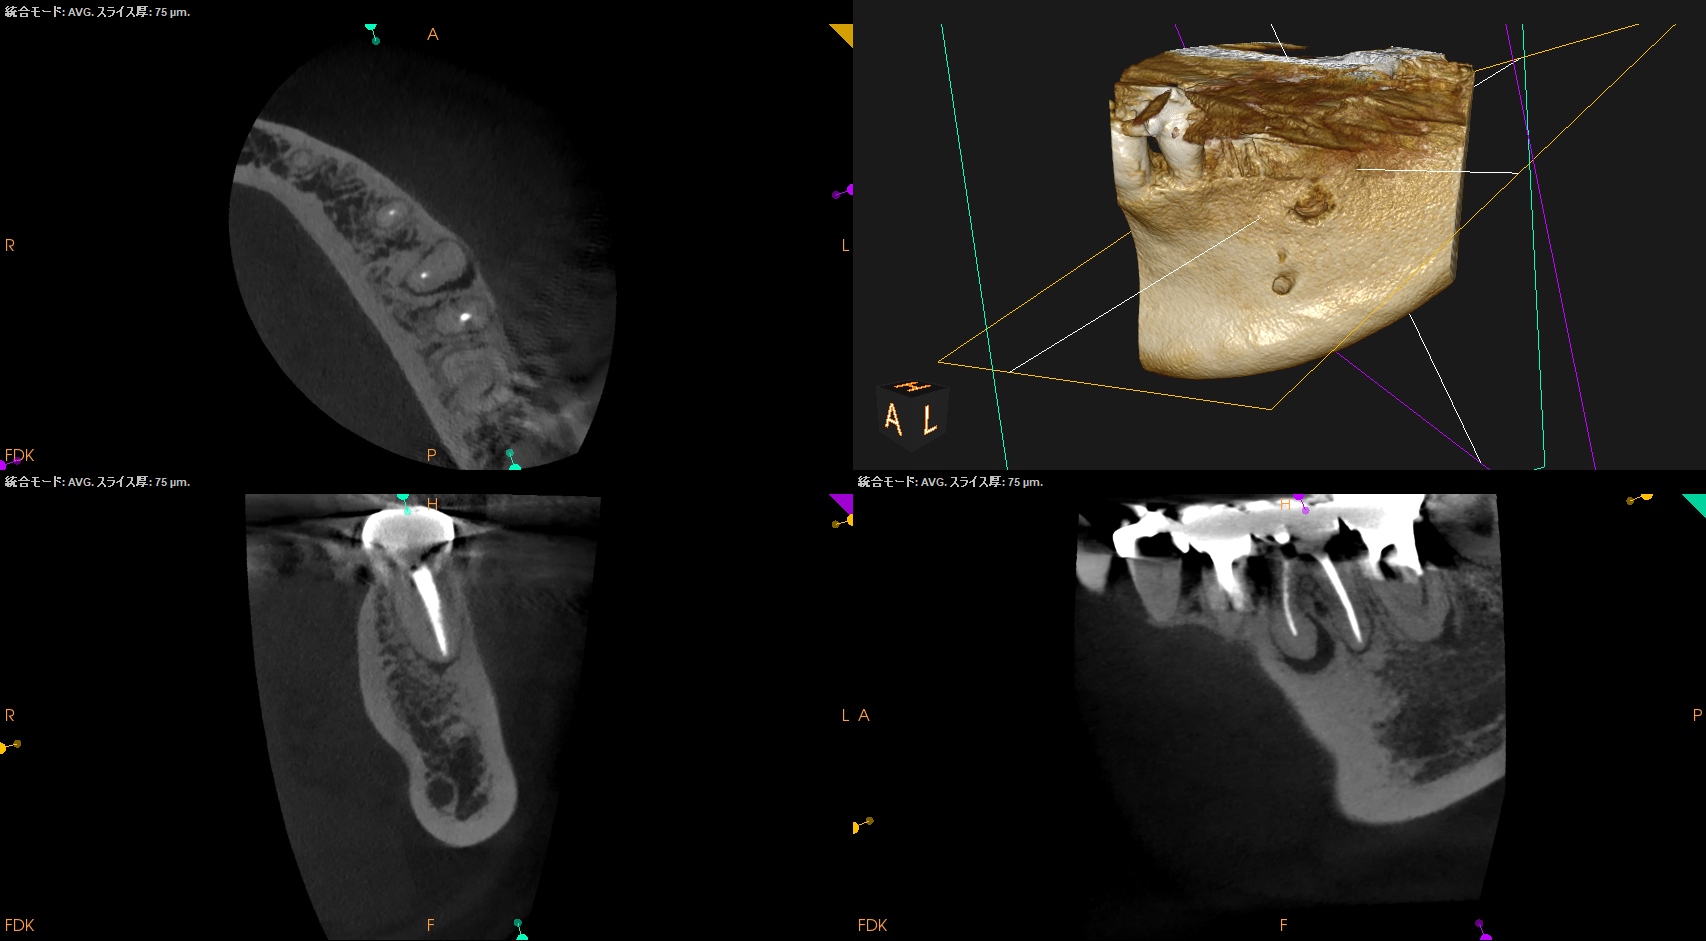

Pre-op CBCT(2025.1.10)

MB

ML

D

根尖病変があるのは近心根のみであるので近心根のみ再根管形成することにした。

その際は、

MBもMLも穿通させる必要があることがCBCTを見える絵にしていけばわかる。

が、世の中のほとんどの人はこの作業ができない。

ほとんどの人はCBCTを保持しているけれども。